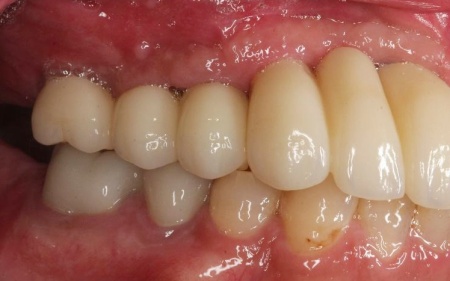

治療後

インプラントが骨にしっかりとなじんだことを確認したら、白くて強度の高い人工歯「ジルコニアクラウン」を装着しました。

他院で治療を行った左下奥歯3本のインプラントは、土台をそのまま活かして人工歯だけ作り直し、噛み合わせを調整します。

左下奥歯1本、右下奥歯2本に装着されていた古い被せ物はすべて外し、ジルコニアクラウンと交換しました。